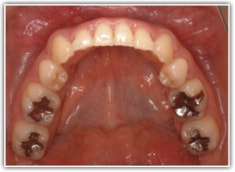

治療後(2年3ヶ月後)

歯根のパラレリング(平行性)が獲得されております。

下顎8番は、両側抜歯済みです。